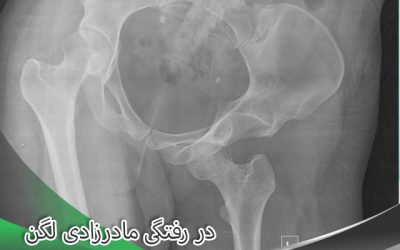

در رفتگی مادرزادی لگن درمان دارد؟

در حالت طبیعی سراستخوان ران در داخل حفره ای به نام حفره استابولوم قرار دارد. ولی در مواردی شاهد هستیم که فرد از بدو تولد و به طور مادرزادی در نحوه قرار گیری استخوان در این حفره با مشکلاتی روبرو است....